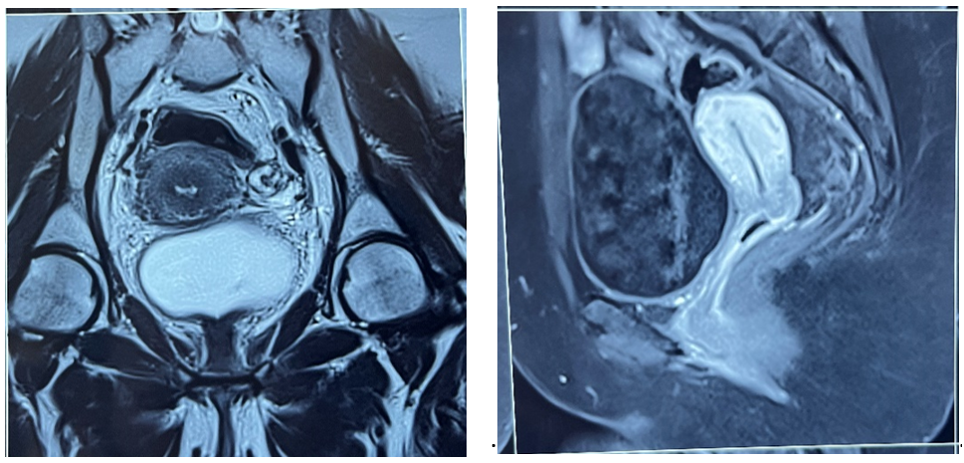

A follow-up pelvic MRI showed an almost complete response after treatment (figures 3-4).

Figure 3-4: Control MRI (post concomitant radio chemotherapy + brachytherapy) showing almost complete response